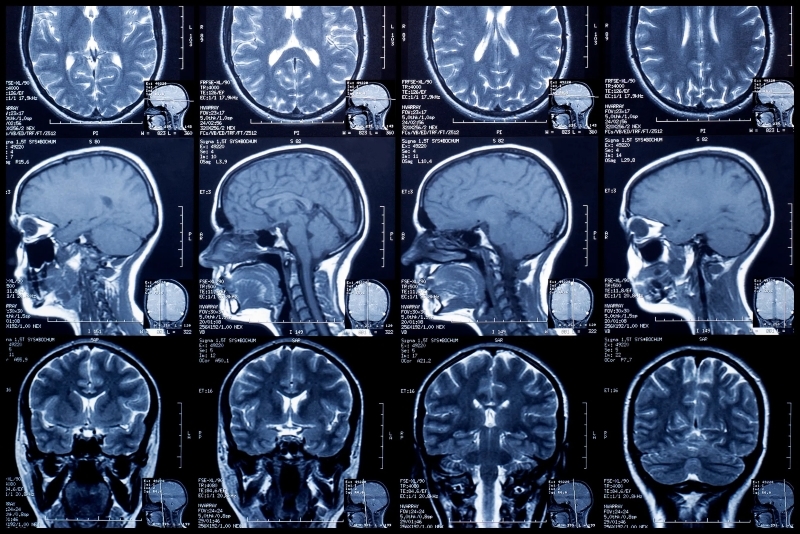

Chụp cộng hưởng từ là kỹ thuật tiên tiến sử dụng từ trường mạnh, sóng radio và máy tính để tạo ra hình ảnh chi tiết bên trong cơ thể. Nhờ đó, bác sĩ có thể đánh giá chính xác tình trạng sức khỏe hoặc theo dõi hiệu quả điều trị của người bệnh. Khác với X-quang và chụp cắt lớp vi tính, MRI không sử dụng bức xạ ion hóa, đảm bảo an toàn hơn cho cơ thể.

Máy MRI hoạt động bằng cách tạo ra từ trường mạnh, sau đó thu nhận tín hiệu phản hồi để dựng thành loạt hình ảnh lát cắt chi tiết. Phương pháp này được ứng dụng rộng rãi trong chẩn đoán nhiều bộ phận cơ thể như não, tim, phổi, đầu gối… và đặc biệt có giá trị trong việc quan sát mô mềm và hệ thần kinh.

Máy MRI hoạt động bằng cách tạo ra từ trường mạnh, sau đó thu nhận tín hiệu phản hồi để dựng thành loạt hình ảnh lát cắt chi tiết